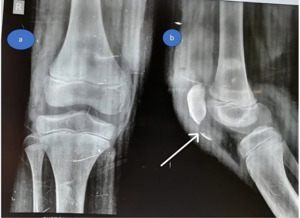

Investigations

At the emergency room, standard AP and lateral radiographs were performed, which revealed patella alta as well as a small osteochondral fragment at the inferior pole of the patella. (Figure 7). As a result of these radiographic findings, a patellar sleeve fracture was diagnosed.